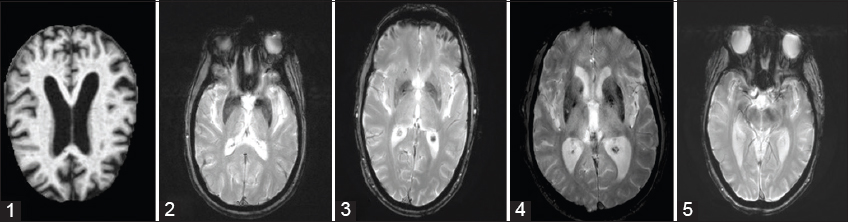

As illustrated in Fig. 1, AD has five stages: (1) AD dementia with severe symptoms, then (2) Late Mild Cognitive Impairment (LMCI), (3) Mild Cognitive Impairment (MCI): which is a condition that precedes dementia but does not meet the criteria for a diagnosis of AD, (4) Early Mild Cognitive Impairment (EMCI), (5) Cognitively Normal (CN): pre-clinical dementia, which is classified by the symptom-free period that occurs between the initial brain lesions and the onset of the first symptoms [7].

Fig. 1. Samples of magnetic resonance imaging images representing different Alzheimer’s disease (AD) stages. (1) AD, (2) Late mild cognitive impairment; (3) Mild cognitive impairment, (4) Early mild cognitive impairment, (5) Cognitively normal.